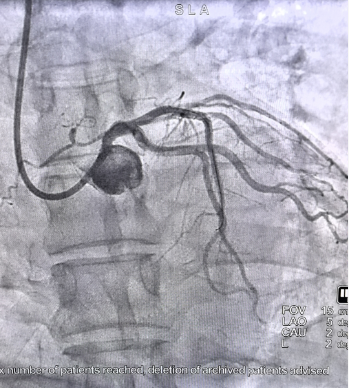

这场抢救不仅是一次本能的职业反应,更是一场依托于日常严格训练、高效协同的应急实战。当天晚间,心血管介入团队罗超、王忠颖医生为患者紧急实施冠状动脉造影。结果显示,患者冠状动脉左主干严重病变,狭窄程度高达99%,残余管腔细如发丝。

△术前术后

左主干被称为心脏的“生命线”,承载着70%以上的心肌供血,术中一旦闭塞将危及生命,手术风险极高。介入团队果断决策,采用高难度的冠脉介入导丝飘入技术:将导丝头端预塑为特定弯形,脱离指引导管支撑,依靠血流动力与导丝弹性,“漂浮”进入极度狭窄的血管。最终,手术成功实施,闭塞血管被顺利开通。